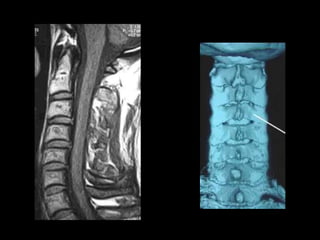

This document provides an overview of normal musculoskeletal imaging. It discusses basic x-ray concepts and densities. It then reviews normal anatomy as seen on x-rays of the skull, spine, pelvis, chest, and extremities. Key anatomical structures are labeled on example x-rays for the shoulder, hip, knee, and foot. Quizzes are included to test recognition of anatomical structures and patient age based on x-rays.